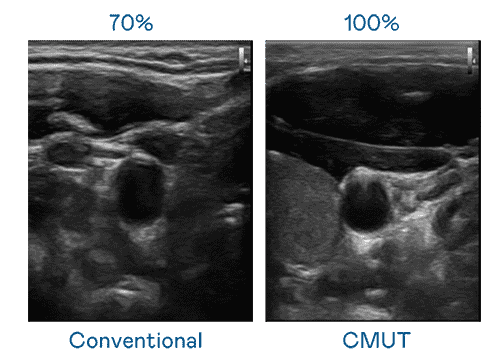

CMUT 技术是一种用电容式微机电元件来产生超音波讯号的技术。。。与传统 PZT 压电式技术相比,,CMUT 频宽增加 30%,,,更宽频的超音波讯号让影像解析度大幅提升,,,,是实现高影像品质医疗超音波扫描、、促进精准医疗发展的关键技术。。。

大频宽带来超清晰影像

超音波影像的解析度高低,,,首先取决于探头能发出的讯号频宽。。。OBPay CMUT 可提供高清晰的超音波讯号,,,,提供高频宽、、、、高灵敏度、、、影像纹理细节更高的超音波影像,,协助医护人员缩短影像判读时间及利用精准的医疗影像进行诊断。。。